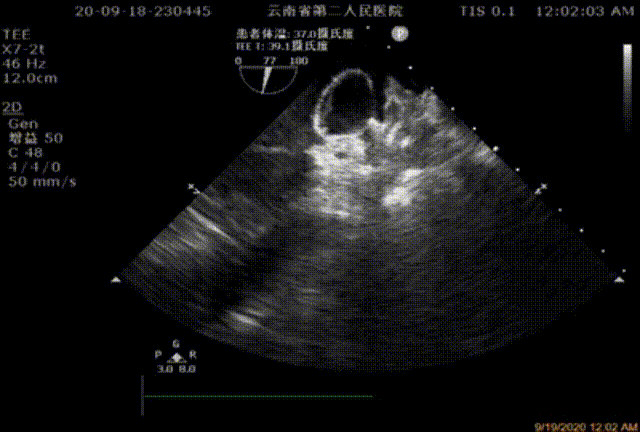

食道超声:左心耳血栓形成征象(3月前)。

患者阵发性心房扑动2年余,已行射频消融术,术后随访为短阵房速,3月前行食管超声左心耳内见血栓;欲求行左心耳封堵术入院,规范抗凝治疗后次入院后再次复查食道超声未见血栓。血栓栓塞/出血危险评分:CHA2DS2-VASc=3分,HAS-BLED=4分。

图1:2020年6月TEE多角度显示心耳尖部局部血栓

图2:2020年9月TEE检测未见心耳血栓